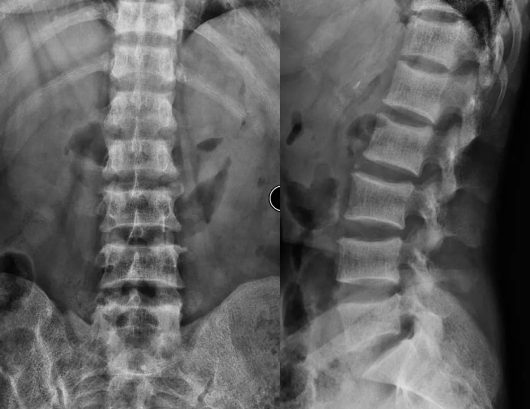

椎体夹心饼征!